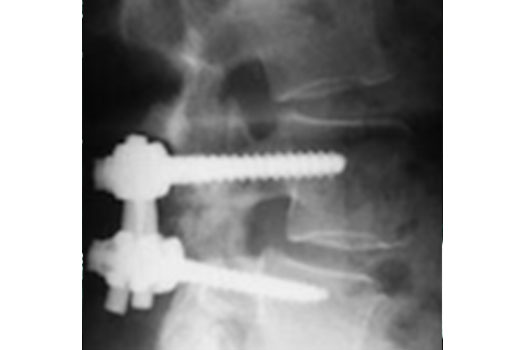

Laminectomie et arthrodèse

En cas de Sténose lombaire associée à un Spondylolisthesis